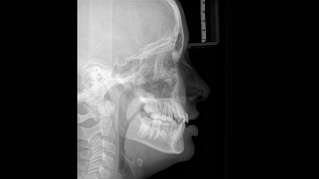

Nós desenvolvemos um conceito de 10 pontos para posicionamento do paciente e imagem de raio-X. Nosso conceito tem como base: imagem de alta qualidade e conforto para o paciente e do assistente. Este conceito auxilia e fornece as ferramentas necessárias para garantir imagens de alta qualidade para análise de tratamento e foca na ergonomia e conforto para o paciente e assistente. A tecnologia patenteada de bloqueio de mordida, por exemplo, estabelece automaticamente a inclinação correta da cabeça do paciente, posicionando o paciente no plano oclusal, em parceria com a fixação da cabeça de 3 pontos e alças firmes para garantir um posicionamento estável - limitando correções desnecessárias.